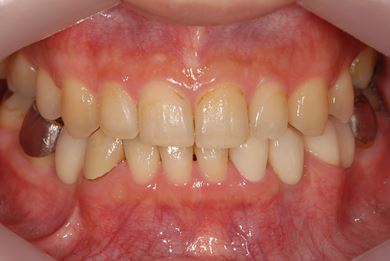

骨再生インプラント治療

| 性別/年齢 | 男性 / 34歳 | ||||||||||||||||||||||||||||||||

| 治療方針 | ソケットリフトにて上顎洞を拳上し、インプラント治療を可能にする。 | ||||||||||||||||||||||||||||||||

| 治療内容 | インプラント1本(ソケットリフト)、メタルボンドセラミッククラウン1本 | ||||||||||||||||||||||||||||||||

| 総治療費 | 547,838円 | ||||||||||||||||||||||||||||||||

| 治療期間 | 4ヶ月 |